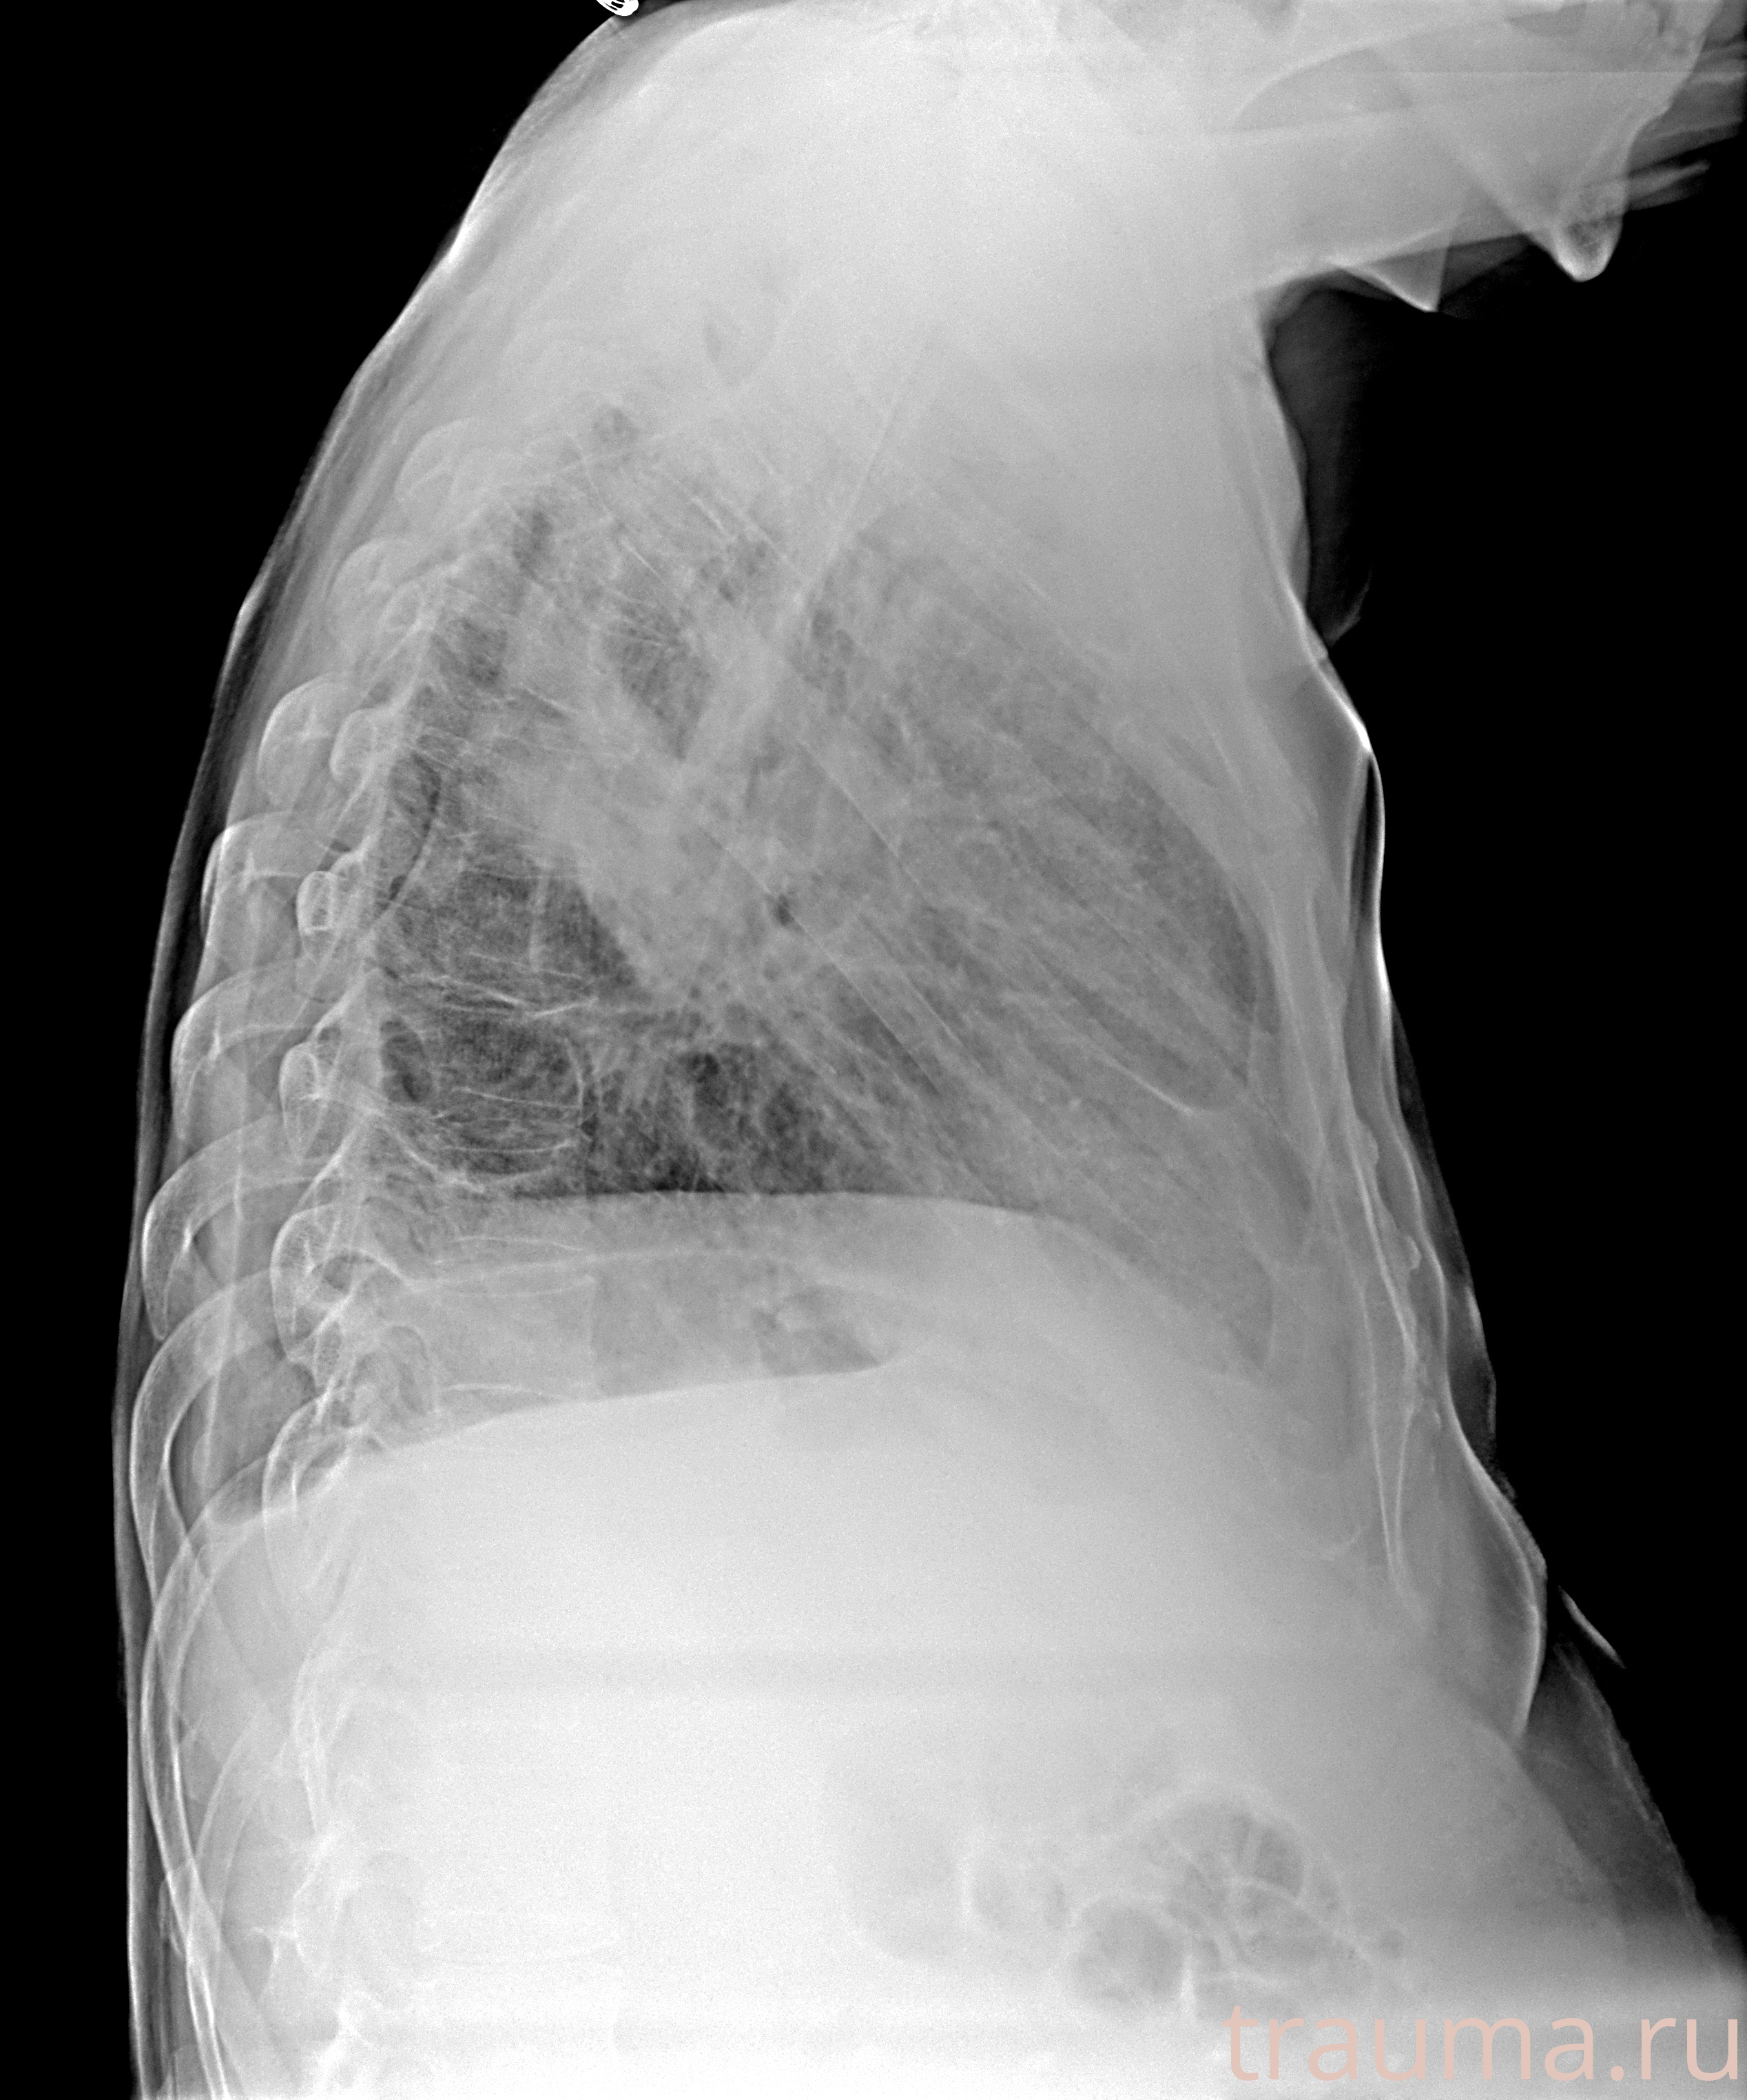

Рентгенограммы

Рентген на дому: по вашему адресу приезжает врач-рентгенолог, травматолог-ортопед с мобильным рентгеновским аппаратом, проводит диагностику травмы или заболевания, делает необходимые рентгенограммы, дает рекомендации по дальнейшему лечению. Получить качественные снимки в домашних условиях возможно благодаря уникальной методике, разработанной МосРентген Центром для института  Склифосовского